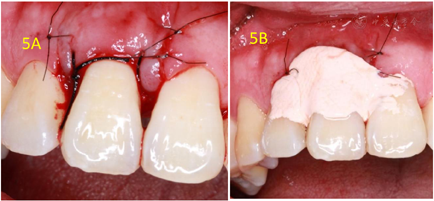

初诊4周后复查(2017年11月8日):检查:11舌侧暂封在,叩痛(-),Ⅰ度松动,唇侧牙周袋仍溢脓。处置:11拟翻瓣探查,翻瓣后11唇侧及近中见大量肉芽,刮治后11近中唇侧根中部见隐裂(图3),快机裂钻磨除隐裂(图4A),填MTA(图4B),填充骨粉后缝合(图5A),上牙周塞治剂(图5B)。

翻瓣探查术后3个月复查(2018年2月28日):检查:11舌侧暂封在,叩痛(-),Ⅰ-松动,唇侧龈退缩3 mm,牙龈充血,近中唇侧位点PD5 mm,余位点2~3 mm,见图6。X线片示:11近中骨质吸收已大部分恢复,见图7A。处置:11上橡皮障,3%次氯酸钠+生理盐水冲洗,干燥,Iroot SP+牙胶尖根充完成根管治疗见图7B,酸蚀粘接,树脂充填,调